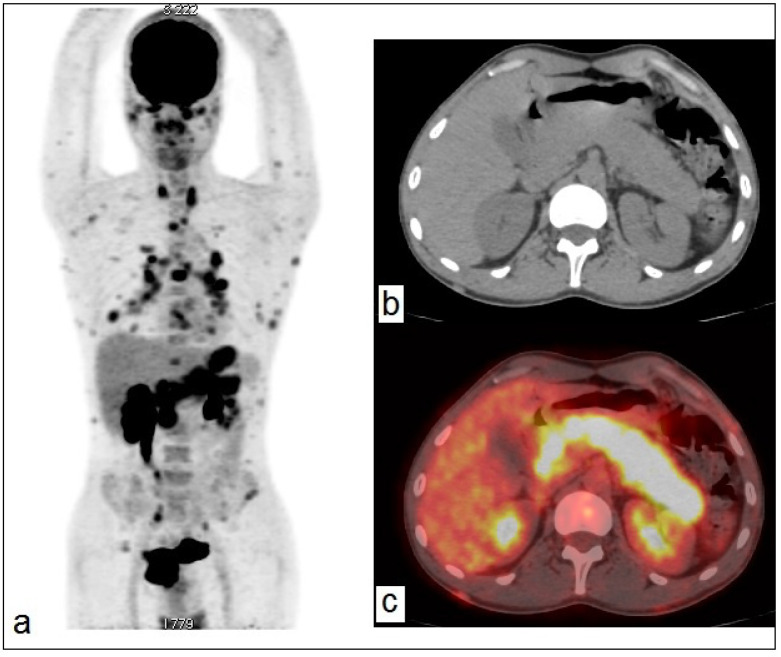

滤泡性淋巴瘤(FL)在临床上被归类为一种常见的惰性非霍奇金淋巴瘤。FL一般为无痛性,预后良好,可累及多种结外部位,包括胃肠道、骨髓、脾脏、肝脏、皮肤等器官。继发累及胰腺的FL是罕见的。我们报告一例FL患者,其初始氟氧葡萄糖正电子发射断层扫描/计算机断层扫描(FDG-PET/CT)显示膈下受累并孤立的弥漫性胰腺高代谢。这一罕见部位的发现凸显了FDG-PET/CT在淋巴瘤分期中的作用。

Follicular lymphoma (FL) is clinically classified as a common type of indolent non-Hodgkin's lymphoma. FL is generally indolent and has good prognosis, it can involve a variety of extranodal sites, including the gastrointestinal tract, bone marrow, spleen, liver, skin, and other organs. Secondary involvement of pancreas in FL is rare. We report the case of a patient with FL whose initial fluorodeoxyglucose-positron emission tomography/computed tomography (FDG-PET/CT) revealed subdiaphragmatic involvement with isolated diffuse pancreatic hypermetabolism. Uncovering such rare site highlights the role of FDG-PET/CT in staging of lymphomas.